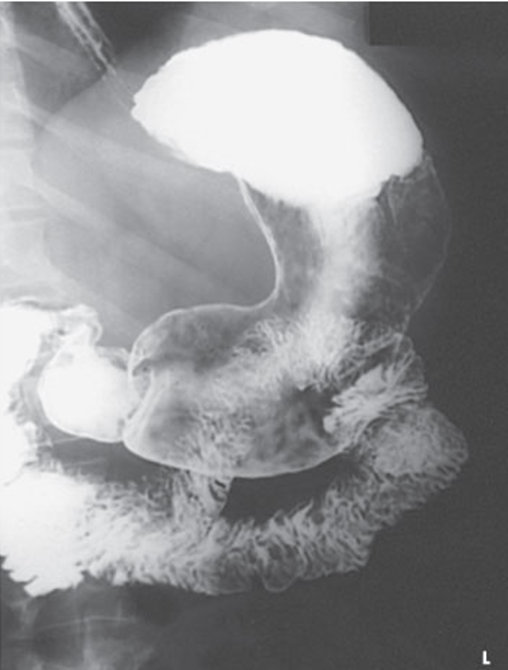

from netrf.org

Learn About Gastrointestinal Neuroendcrine Tumors NETRF